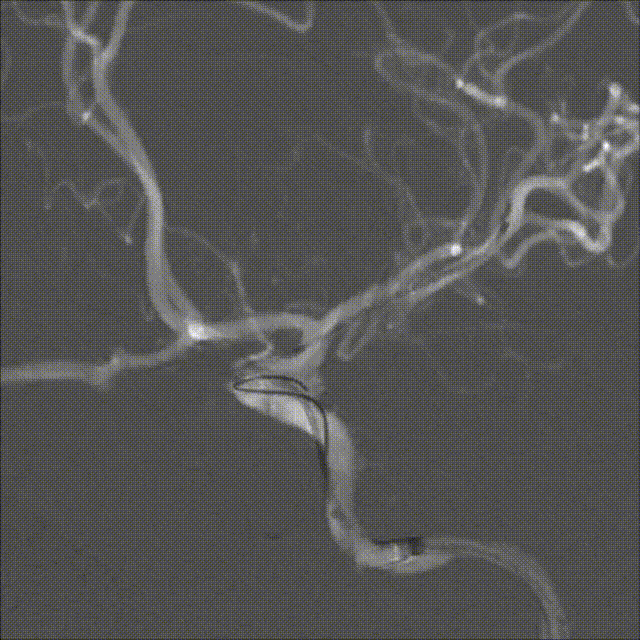

术后影像

➢术后工作位造影

病人术后:动脉瘤已完全栓塞,瘤体不显影,载瘤动脉通畅。